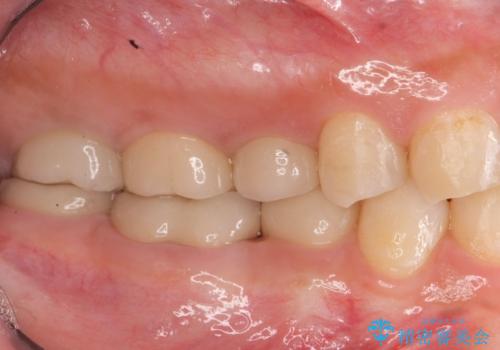

見える銀歯を白く 下顎セラミックブリッジ治療

- 笑った時に見える銀歯を白くしたいとの希望で来院されました。

インレータイプのブリッジが装着されており、虫歯の再発が起きやすいような状況に見受けられたので、ジルコニアを用いたクラウンタイプのブリッジの製作による審美性の改善を計画します。